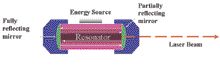

Since its invention in 1960, the laser has found a wide range of applications in medicine. It took more than 25 years to see the first dental laser, with very limited use, in our office. Since then, various types of lasers for dental treatments (Nd YAG, CO2, Diode, Er,Cr:YSGG and ErYAG) have been developed and … Read more